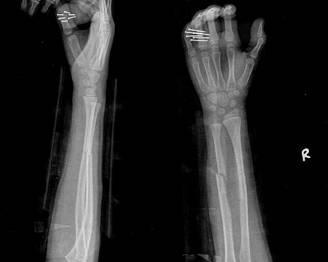

摘要:最新尺橈骨融合方法展現(xiàn)骨頭間的奇妙和諧與友情力量。通過先進的醫(yī)療技術,尺骨和橈骨之間的融合得到顯著改善。這種方法不僅提高了治療效果,還展現(xiàn)了人體骨骼之間的和諧關系。憑借友情和信念的力量,醫(yī)學界不斷突破,為患者帶來福音。

經過醫(yī)生的診斷,小明被確診為尺橈骨融合,這是一種骨骼疾病,會導致尺骨和橈骨無法正?;顒?,聽到這個消息后,小明和他的朋友們都感到有些緊張和害怕,但他們并沒有放棄,而是選擇相互鼓勵,共同面對這個挑戰(zhàn)。

在醫(yī)生的介紹下,他們了解到了一種最新的尺橈骨融合治療方法——通過微創(chuàng)手術進行骨骼融合的新技術,這種方法不僅減少了手術風險,還能更快地恢復活動能力,雖然小明感到害怕,但他的朋友們一直陪伴在他身邊,給予他勇氣和力量。